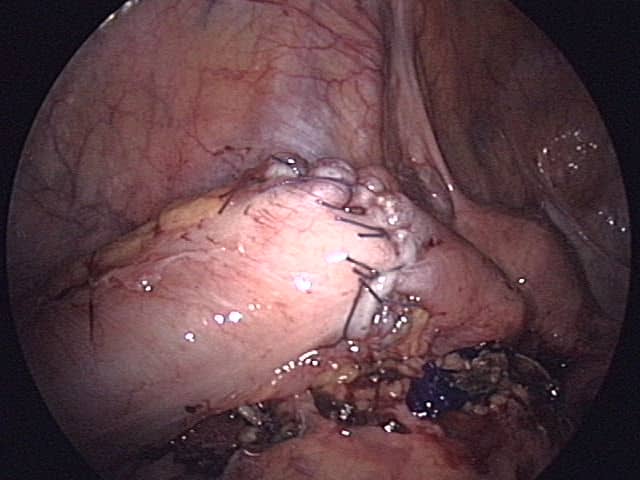

Patients who are systemically unwell, signs of pertonism, and/or with large leaks will require surgical intervention to ensure appropriate source control. This will typically require a laparotomy, washout of the contamination, and refashioning of the anastomosis and/or formation of a defunctioning proximal stoma.

Figure 2 – A hand-sewn anastomosis of the sigmoid colon